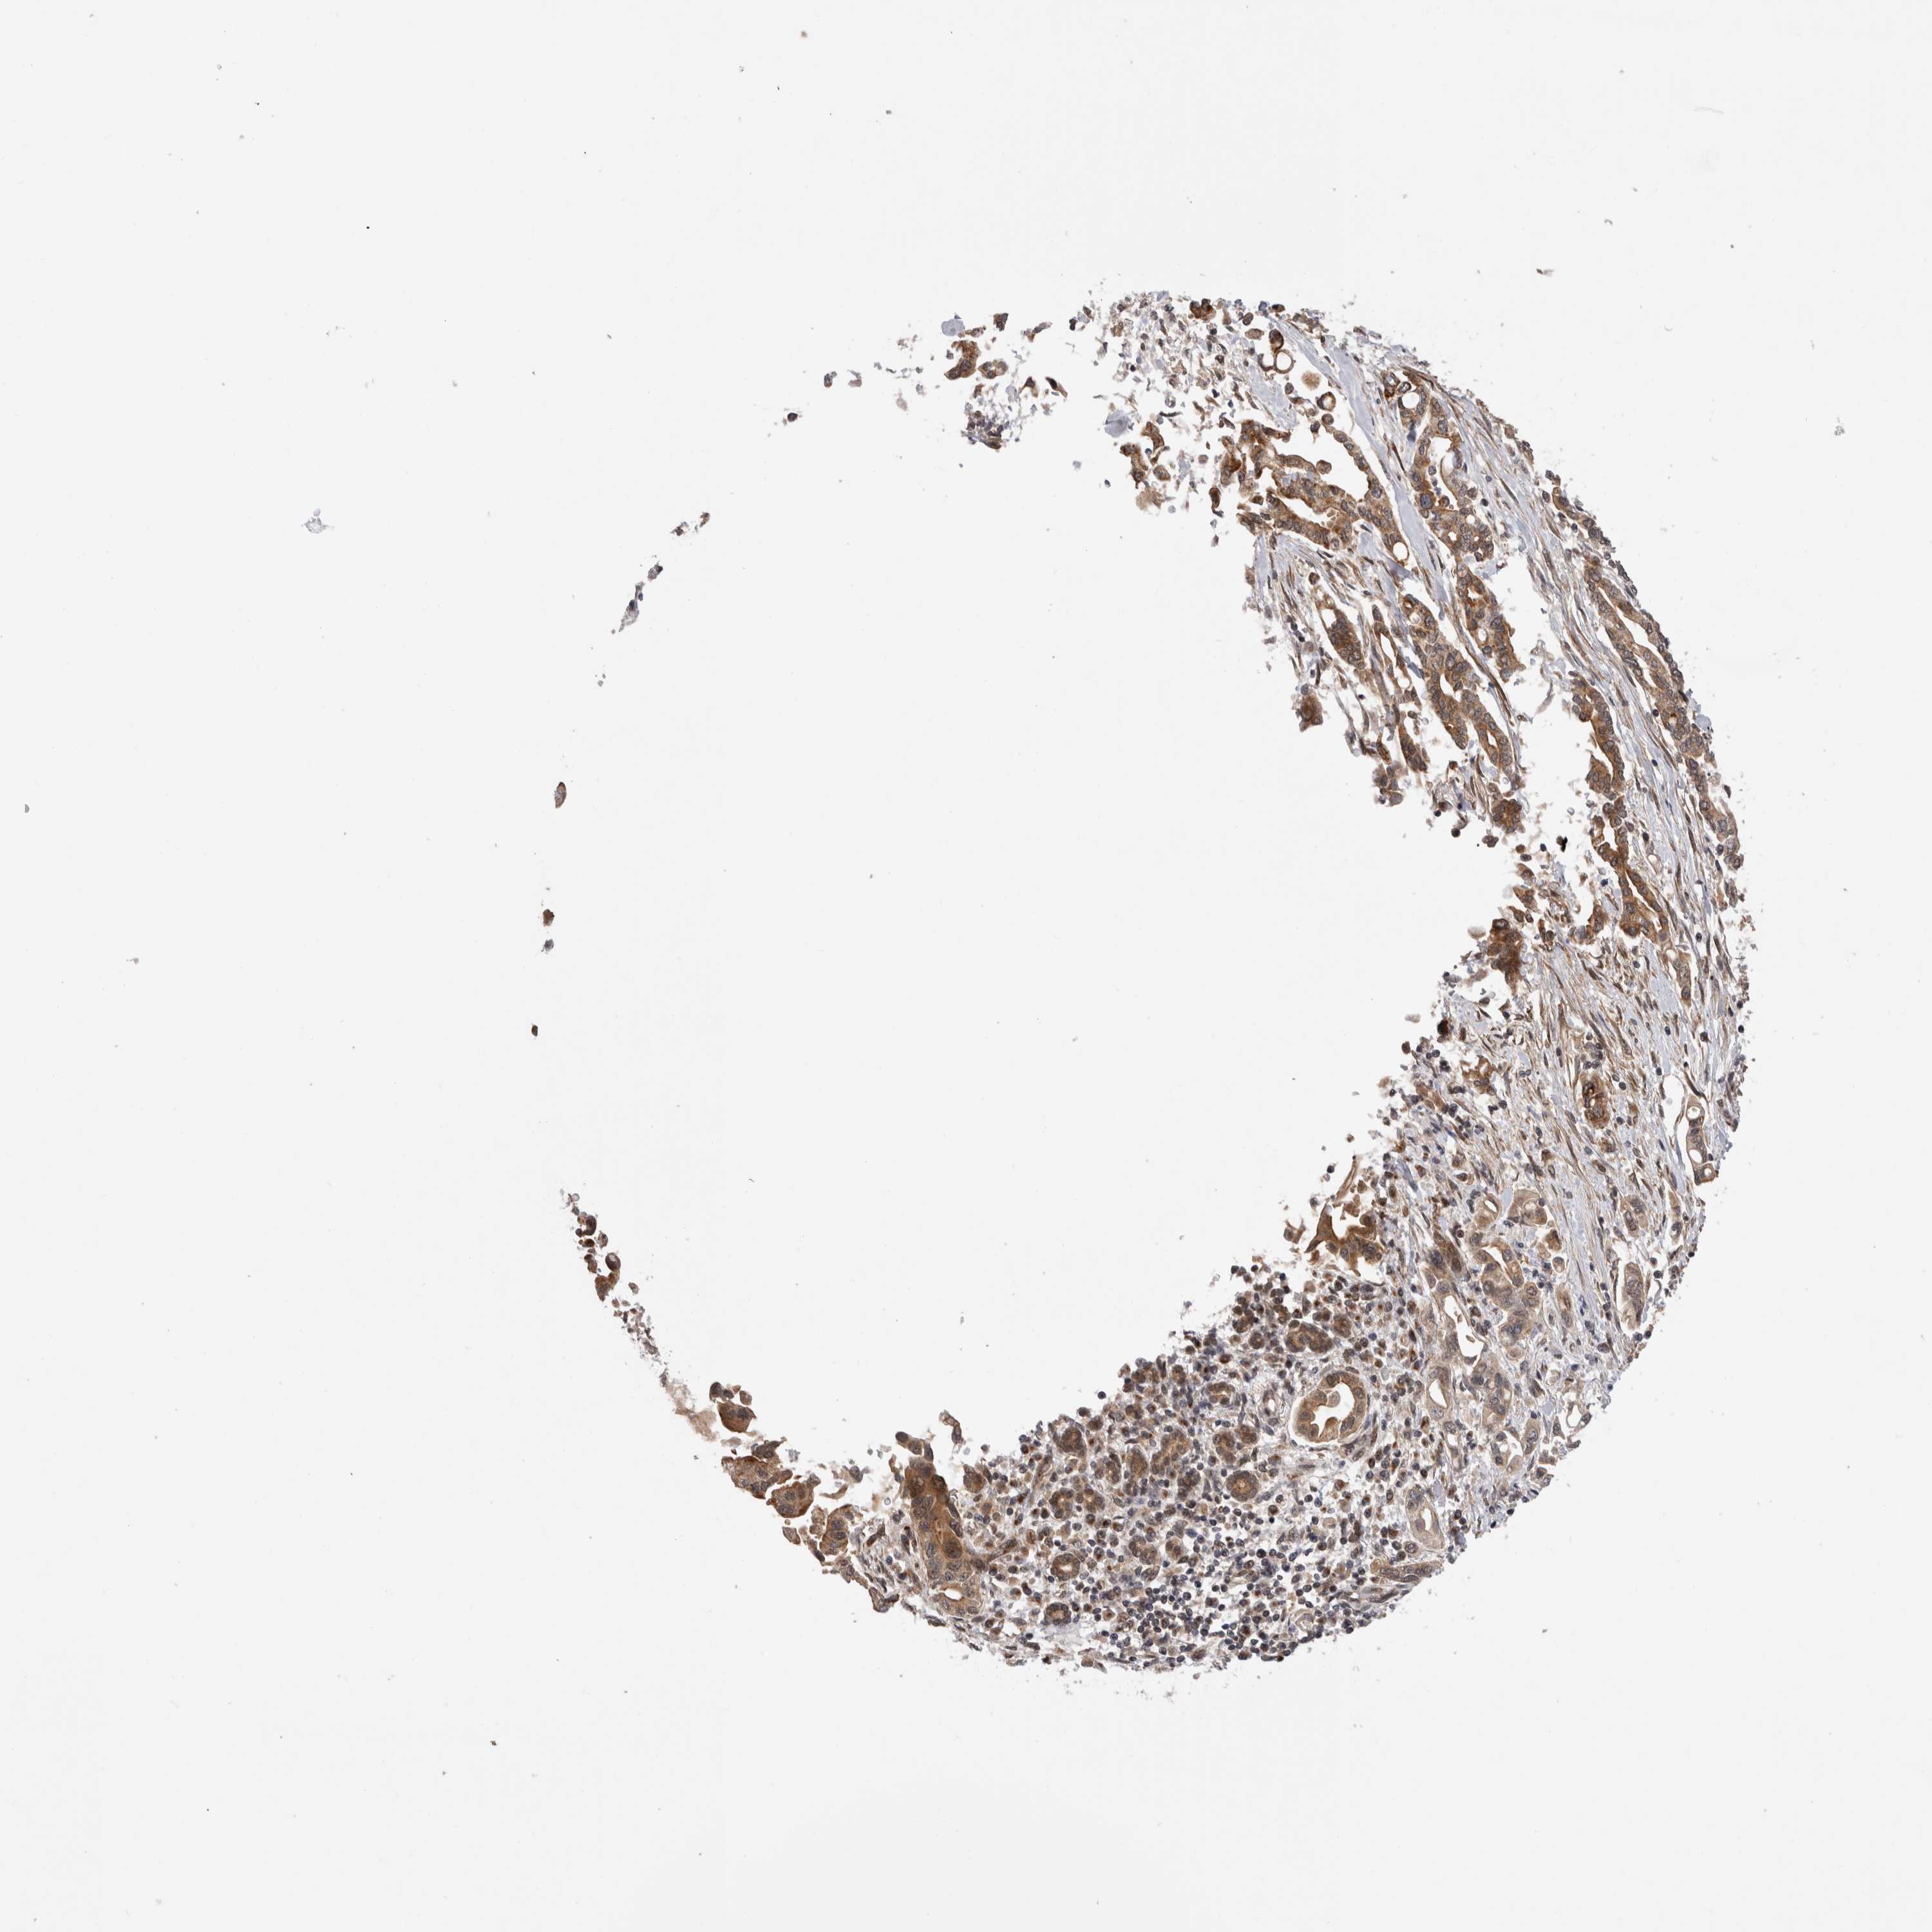

PANCREATIC CANCER - Protein expressioni

A mouse-over function shows sample information and annotation data. Click on an image to view it in a full screen mode. Samples can be filtered based on level of antibody staining by selecting one or several of the following categories: high, medium, low and not detected. The assay and annotation is described here.

Note that samples used for immunohistochemistry by the Human Protein Atlas do not correspond to samples in the TCGA dataset.

Antibody stainingi

Antibody staining in the annotated cell types in the current human tissue is reported as not detected, low, medium, or high, based on conventional immunohistochemistry profiling in selected tissues. This score is based on the combination of the staining intensity and fraction of stained cells.

Each image is clickable and will lead to virtual microscopy that enables deeper exploration of all samples and also displays staining intensity scores, fraction scores and subcellular localization as well as patient and tissue information for each sample.

Antibody HPA025020

Staining

High

Medium

Low

Not detected

Intensity

Strong

Moderate

Weak

Negative

Quantity

>75%

75%-25%

<25%

None

Location

Nuclear

Cytoplasmic/membranous

Cytoplasmic/membranous,nuclear

Adenocarcinoma, NOS